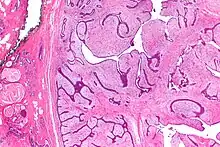

Micrograph of a phyllodes tumor (right of image) with the characteristic long clefts and myxoid cellular stroma. Normal breast and fibrocystic change are also seen (left of image). H&E stain.

Phullon means 'leaf' in Greek. It is appropriately named to describe the characteristic papillary projections seen on histology in phyllodes tumors.

Phyllodes tumors (from Greek: phullon), are a rare type of biphasic fibroepithelial mass that form from the periductal stromal and epithelial cells of the breast.[1] They account for less than 1% of all breast neoplasms.[2] They were previously termed cystosarcoma phyllodes, coined by Johannes Müller in 1838, before being renamed to phyllodes tumor by the World Health Organization in 2003.[3] Phullon, which means 'leaf' in Greek, describes the unique papillary projections characteristic of phyllodes tumors on histology.[1] Diagnosis is made via a core-needle biopsy and treatment is typically surgical resection with wide margins (>1 cm), due to their propensity to recur.[4]